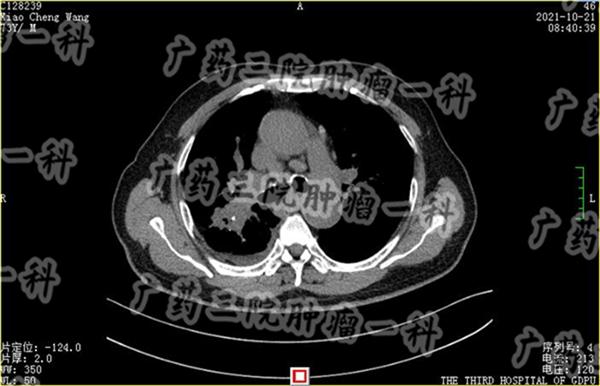

肺癌发展到IV期,很可能是已经出现了转移,有的患者甚至不止一处转移。此时的肺癌患者,开刀手术治疗效果有限,而且被癌细胞长时间掠夺营养,患者的身体状态下降,也难以承受开胸手术的副作用。

对这类患者,彭齐荣教授认为,患者可以进行微创综合治理。彭齐荣教授说,此时肺部的癌细胞已经开始扩散到远处,也是治疗最难的一个阶段,具体的治疗方案不能再是单一的某个治疗方式,而应该根据扩散的位置,患者的身体状况,来选择合适的技术,综合考虑,具体实施。

肺癌晚期可能出现肝转移,可能出现骨转移,可能出现淋巴转移等等,不同部位的转移病灶,合适的微创治疗方案不同,广药三院肿瘤科一区医生需要根据患者具体的转移部位,充分利用血管靶向治疗、粒子植入治疗、微波消融治疗、冷冻消融治疗等不同的微创治疗技术,制定合适的治疗方案。